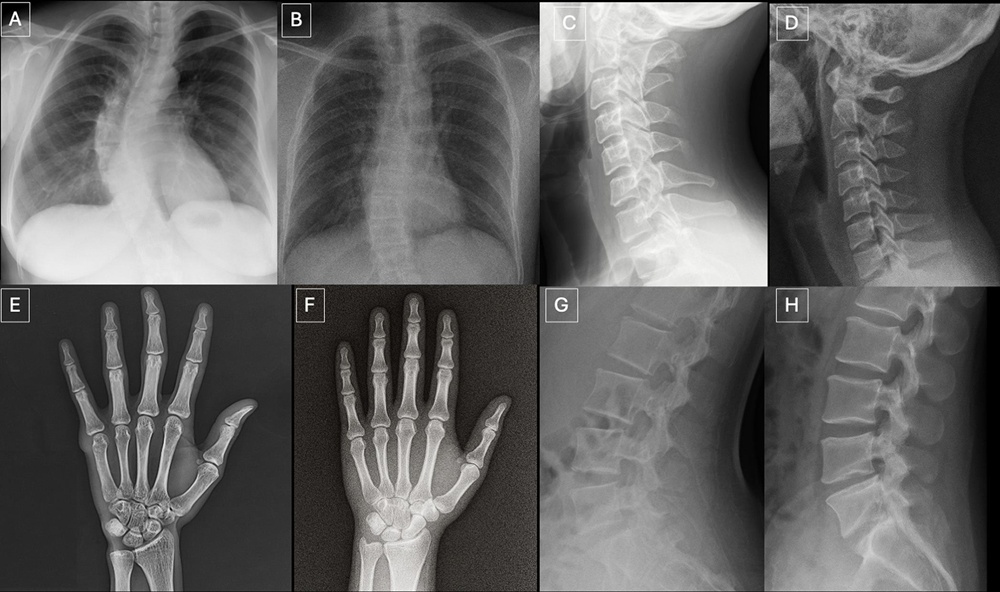

▲ 這些成對影像顯示,GPT-4o 能在不同解剖區域產生在放射學上看起來合理的影像。(A)真實與(B)GPT-4o 生成的胸腔 X 光片,(C)真實與(D)GPT-4o 生成的頸椎偏位 X 光片,(E)真實與(F)GPT-4o 生成的手部 X 光片,以及(G)真實與(H)GPT-4o 生成的腰椎偏位 X 光片。(Source:論文)